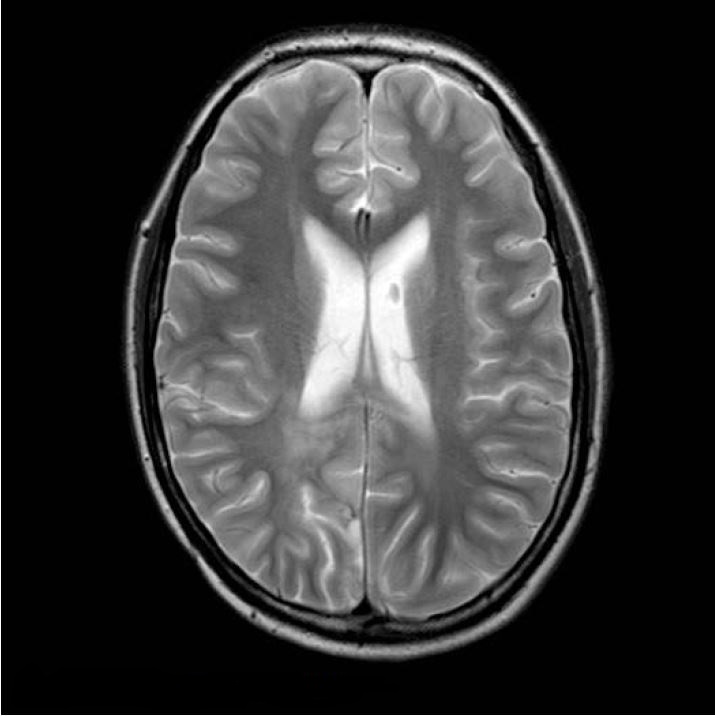

Контрольні МРТ-дослідження залишалися стабільними до липня 2011 року (відразу до кінця супутньої хіміотерапії) (рис. 3 і 4). Потім було проведено додаткове обстеження МРТ (через 4 тижні) з перфузією та МРС.

Рисунок 3 T2WI, липень 2011